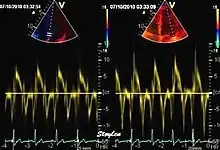

Spectral tissue velocity curves from the mitral annulus at the septal (left) and lateral (right) points. The curves show multiple heartbeats.

Pulsed wave spectral tissue Doppler has become a universal tool that is part of the general echocardiographic examination. Like any other echocardiographic measurement, measures by tissue Doppler should be interpreted in the context of the whole examination. The velocity curves are in general taken from the base of the mitral annulus at the insertion of the mitral leaflets, in the septal and lateral points of the four chamber view, and eventually the anterior and inferior points of the two-chamber views. For the right ventricle it is customary to use the lateral point of the tricuspid annulus only. Averaging peak velocities from the septal and lateral point has become common, although it has been shown that averaging all four points mentioned above, gives significantly less variability[3]